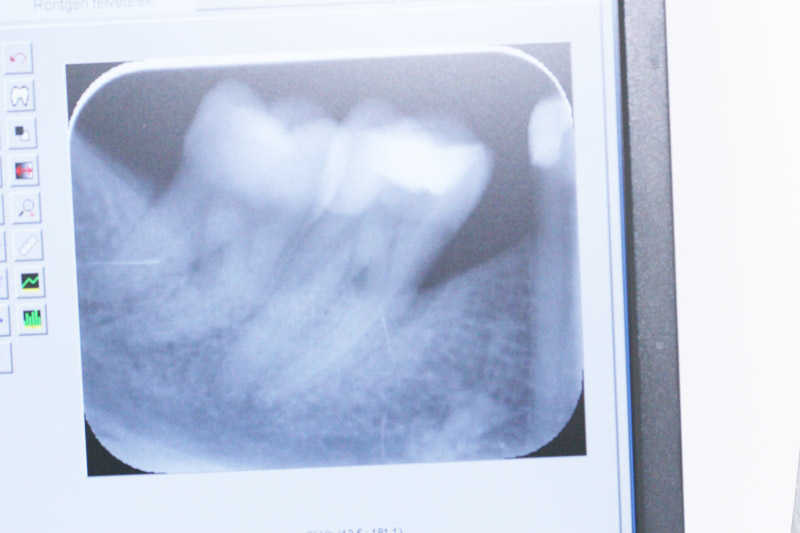

A kiindulási állapot röntgenfelvétele